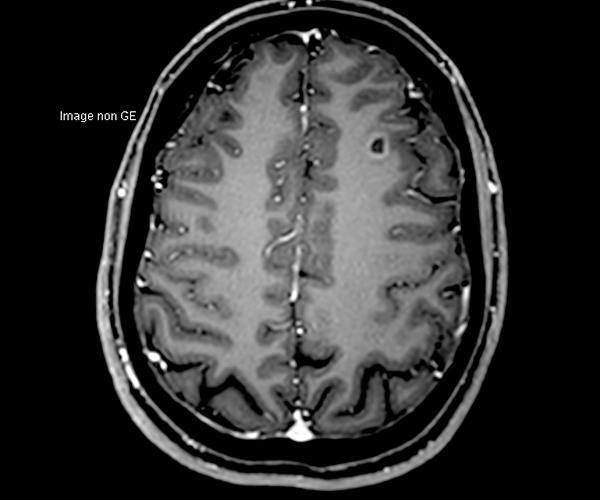

Concernant l’imagerie cérébrale, l’IRM 3T permet d’augmenter la sensibilité de détection de lésions ischémiques aiguës de petite taille, notamment chez les patients adressés pour accident ischémique transitoire (accident vasculaire cérébral), grâce à la séquence de diffusion dont le signal et la résolution sont augmentés.

L’amélioration de la résolution spatiale s’applique à l’exploration morphologique des hippocampes dans le diagnostic de la maladie d’Alzheimer, à la détection de petites lésions de sclérose en plaques ou de métastases, à l’étude fine du cortex dans les épilepsies.